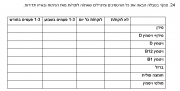

| 18:30, 12 באוקטובר 2017 | GlycoMark3.jpg (קובץ) |  |

17 קילו־בייטים | Motyk | 1 | |

| 18:28, 12 באוקטובר 2017 | GlycoMark2.png (קובץ) |  |

31 קילו־בייטים | Motyk | 1 | |

| 18:27, 12 באוקטובר 2017 | GlycoMark1.png (קובץ) |  |

29 קילו־בייטים | Motyk | 1 | |

| 18:25, 12 באוקטובר 2017 | GlycoMark.png (קובץ) |  |

12 קילו־בייטים | Motyk | 1 | |